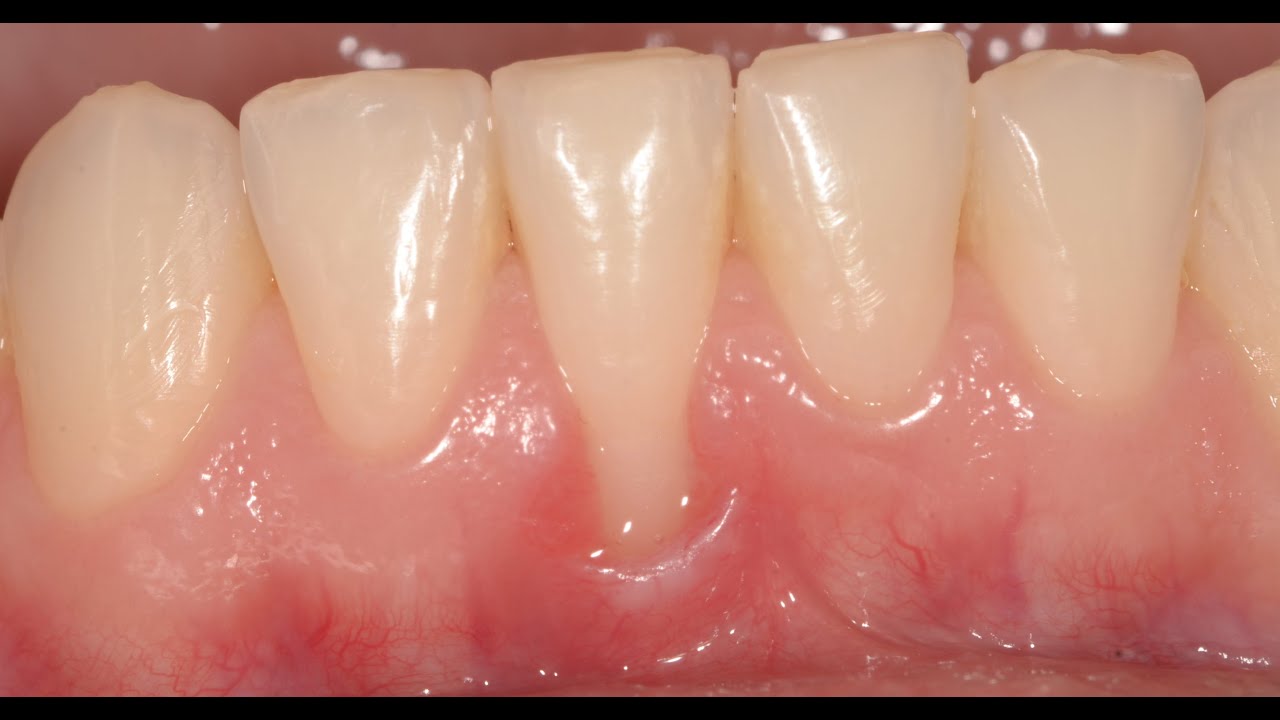

Gum Recession treated with a Connective tissue graft YouTube

Gum Recession treated with a Connective tissue graft YouTube Gum Graft Youtube i had a gum graft which is considered a minor surgery. • learn about gum grafts, a dental procedure that can protect tooth roots,. this 3d medical animation features gingival graft (gum graft). All you need to know! How to ensure optimal and. Robert stanley, from stanley dentistry in cary, north carolina, explains. 245k views 5 years ago.. Gum Graft Youtube.